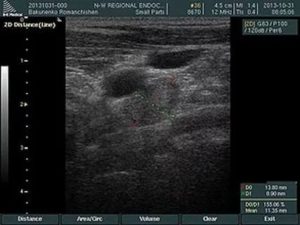

Лимфоузлы исследуют линейным датчиком 7,5-12 МГц. Для осмотра больших конгломератов может пригодиться конвексный датчик 3-5 МГц. Брыжеечные лимфоузлы смотри Мезаденит на УЗИ (лекция на Диагностере).

Нормальный лимфоузел на УЗИ — небольшое (менее 1 см) гипоэхогенное образование с гиперэхогенным рубчиком в центре; бобовидной или овальной формы; контур четкий, ровный или волнистый.

Гипоэхогенная зона по периферии — корковое вещество, гиперэхогенная линейная структура — сосуды, трабекулы, жировые включения, частично мозговое вещество.

В воротах гиперэхогенный треугольник «врезается» в паренхиму, здесь при ЦДК бывает видно сосуды.